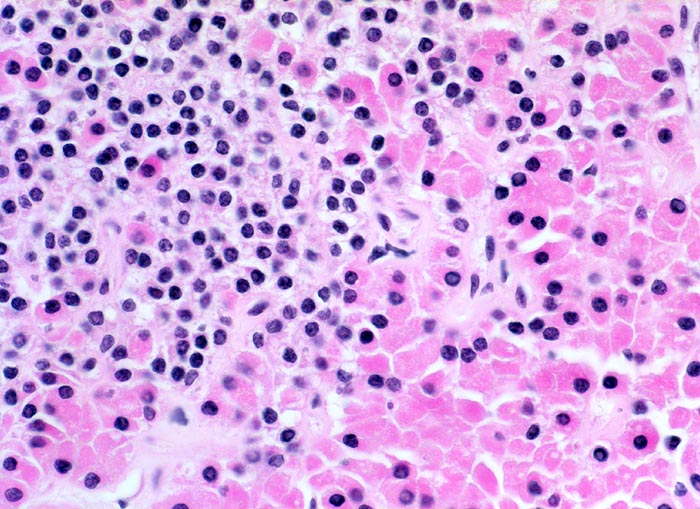

• Knotige vergrösserte Nebenschilddrüse. Abgrenzung der einzelnen Knoten durch breite Fibrosebänder.

• Hyperplasie lipidarmer Hauptzellen.

• Areale mit oxyphilen Zellen.

• Verminderter Fettgehalt (<<35%). Für normale Nebenschilddrüsen gilt: